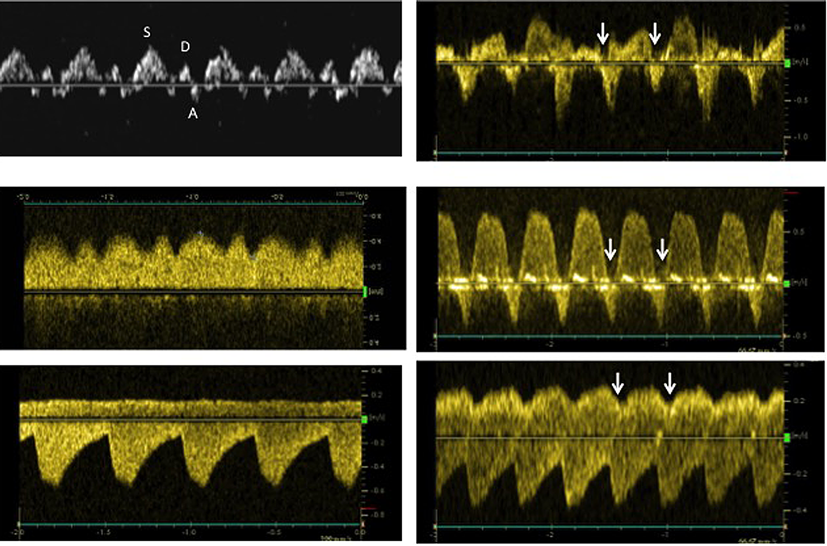

三尖弁輪収縮期移動距離(tricuspid annular plane systolic excursion: TAPSE)は,三尖弁輪右室自由壁側の長軸方向の移動距離をMモード法で計測するものであり,超音波ビームの方向が三尖弁輪の運動方向とできるだけ一致するように注意する必要がある.通常,成人や小児の計測では心尖部四腔断面において,カーソルを右室自由壁の三尖弁輪部に置く.このためまた,カーソルは心尖部から三尖弁輪の対角線に置かれることとなり,心尖部方向の弁輪移動距離を測定することとなる.胎児での計測は,4腔断面において心尖部が6時あるいは12時方向に描出し,心室中隔に平行になるようにカーソルを置き計測するとされている(Fig. 5).つまり心尖部方向への移動距離でなく,弁輪に垂直方向の移動距離を測定することとなる.正常値は21週で3.6 mm,39週で8.6 mmと週数に正の相関を示す9).同様の方法で心機能評価が困難な胎児においては僧帽弁輪収縮期移動距離(mitral annular plane systolic excursion: MAPSE)を評価することで左室機能が評価されているが,TAPSEに比較し報告は少ない.測定方法も成人と同様に心尖部から弁輪の対角線にカーソルを置き測定している報告もあり,TAPSE, MAPSEともに標準的な心機能評価方法にはなっていない10)

Fig. 5 Measurement of the tricuspid annular plane systolic excursion

A: A four-chamber view of the fetal heart. The cursor was placed parallel to the ventricular septum. B: M-mode record of the TV annulus and the measured distance of the TV annulus excursion toward the RV apex. (A: anterior, LV: left ventricle, RA: right atrium, RV: right ventricle, TAPSE: tricuspid annular plane systolic excursion, TV: tricuspid valve)